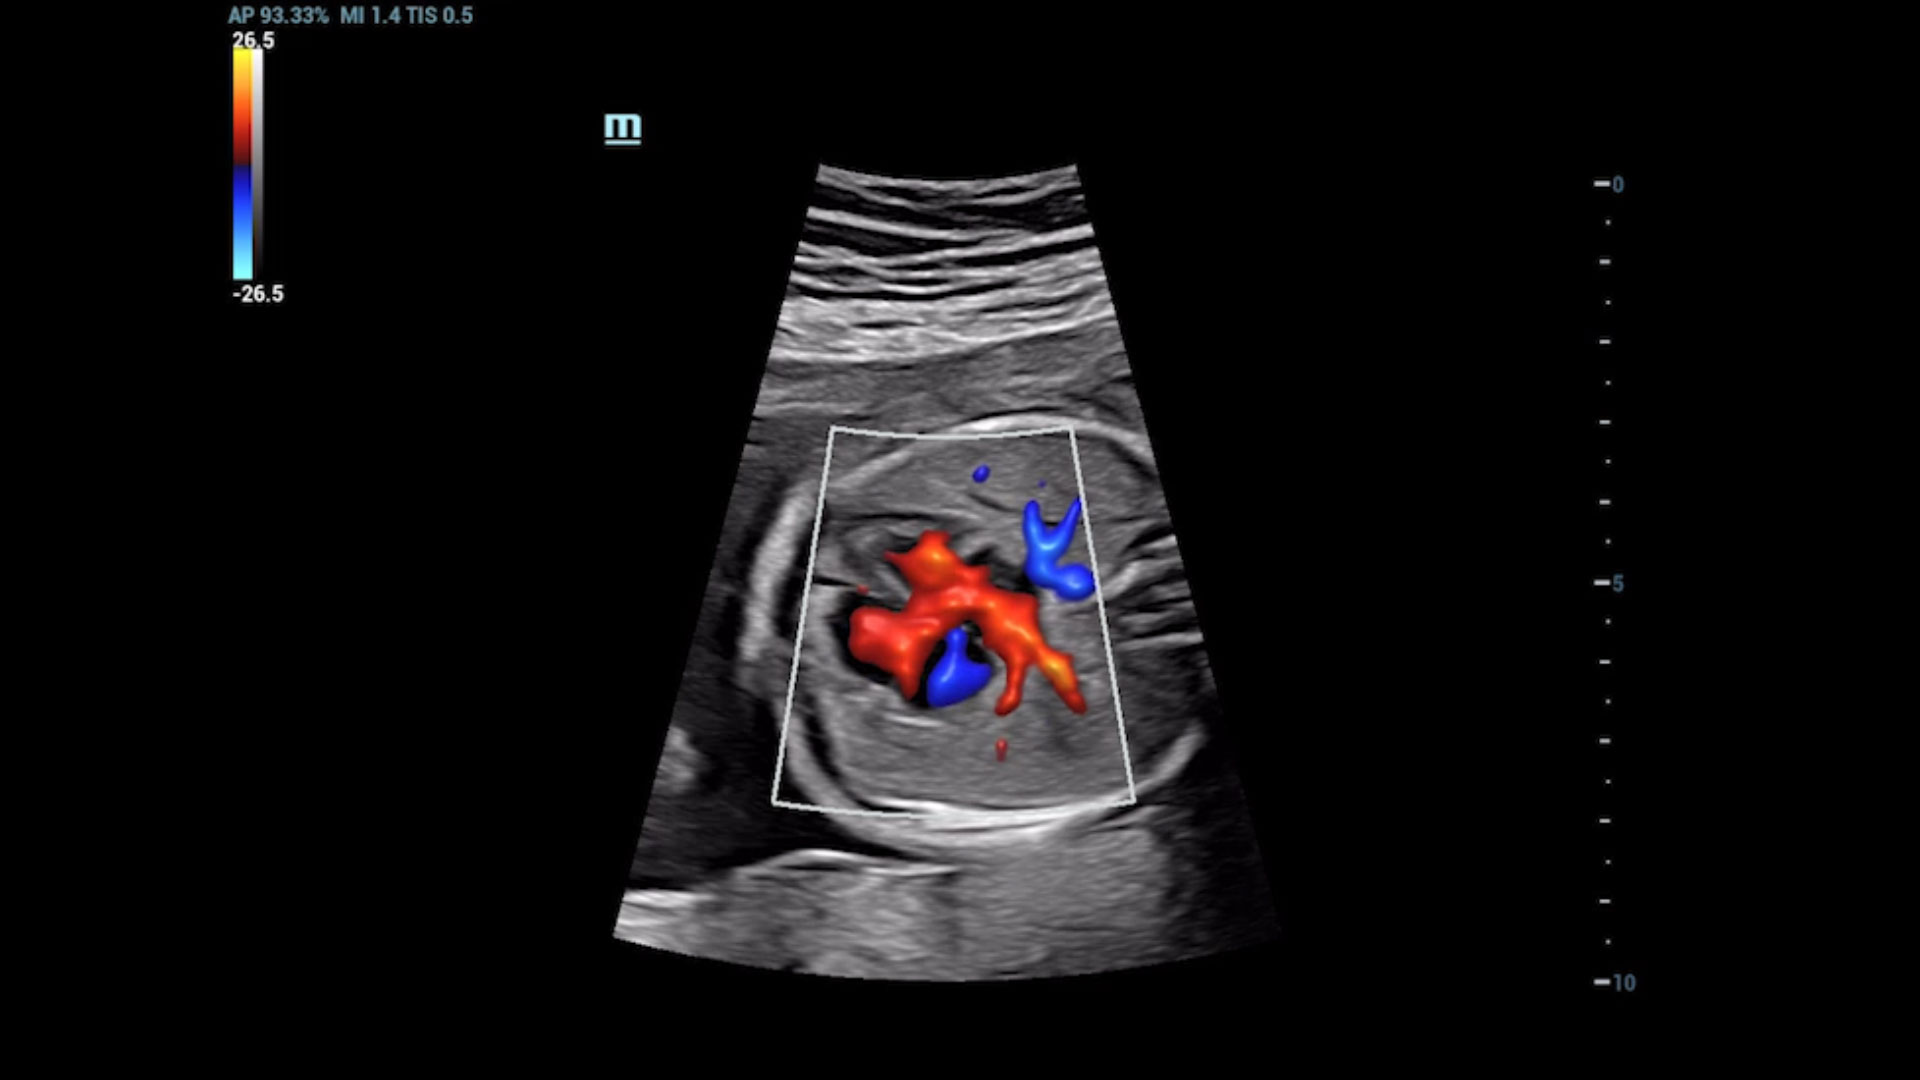

UMA (Ultra-Micro Angiography)

The innovative technology breaks the bottlenecks of traditional Doppler imaging. With ultra-high spatial resolution and flow sensitivity, it allows detecting super-subtle and super-slow flow perfusions, thereby extending the clinical application of qualitative and quantitative ultrasound evaluation in fetal brain, kidney, placenta, endometrium, ovary, etc.

UMA - fetus renal flow

3D UMA - fetus intracranial flow